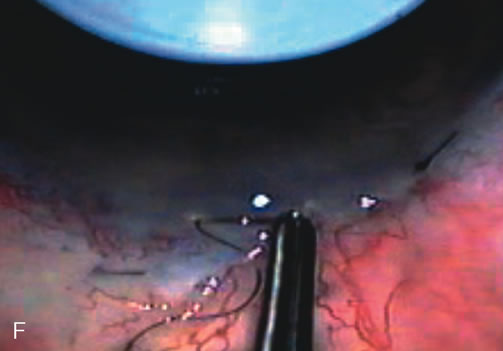

Fig. 7. Phacotrabeculectomy adjacent to a failed filter in cataractous eye. The ability to combine small-incision cataract extraction with trabeculectomy all through the same incision adjacent to the failed filter allows the surgeon to work in a familiar superior area. Avoiding incisions into the existing bleb decreases conjunctival buttonholes, hypotony, operating room time, and subconjunctival bleeding. A. Appearance of failed bleb with exposure of superior temporal quadrant gained with a corneal traction suture. B. Prepare a limbus-based conjunctival flap and a scleral flap. C. This bleb is at high risk to fail again justifying the need for MMC, 0.2 mg/cc applied on a pledget for 4 minutes. D. Insert the keratome and perform phacotrabeculectomy in the usual fashion.